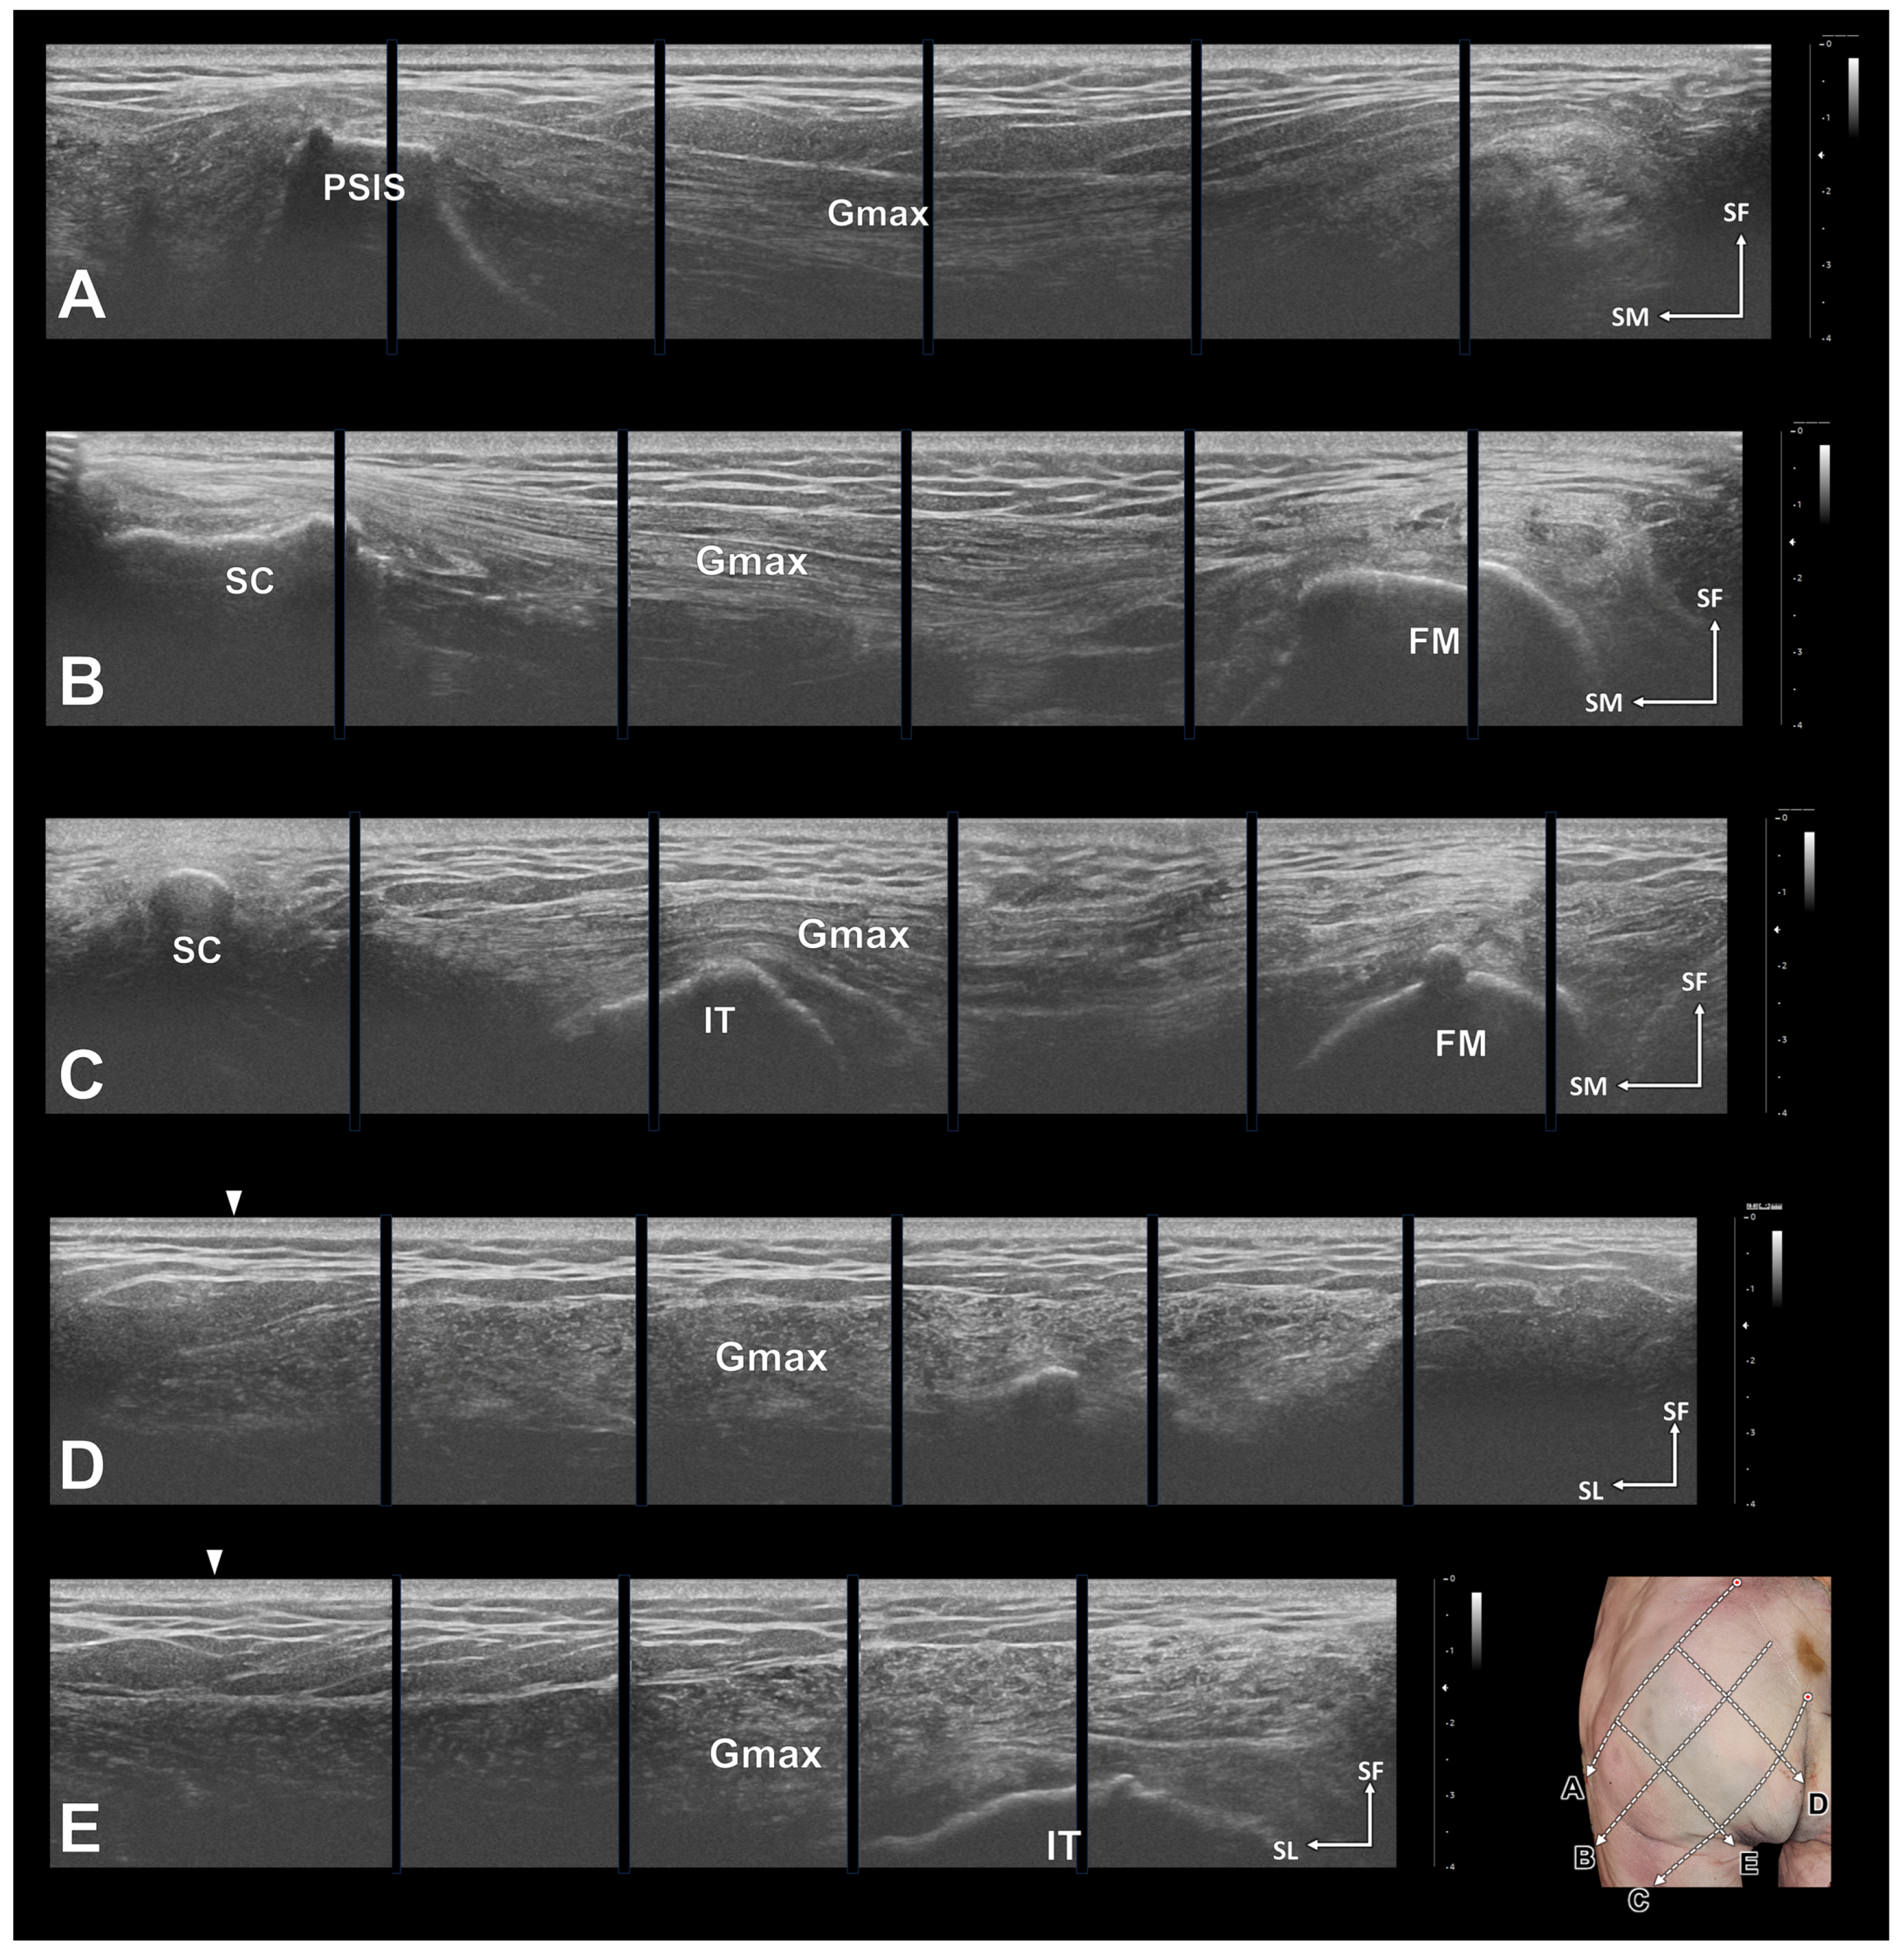

2.2. Ultrasonography and Ultrasound-Guided Injections

3.5. Ultrasonography and Ultrasound-Guided Injections